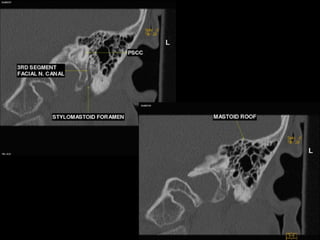

CT Temporal Bone Search Pattern with selected images :

Other structures/landmarks:

•Styloid process

•Stylomastoid foramen

•Petrous apex

•Mastoid air cells

•Sigmoid sinus

•Cochlear promontory

•Carotid canal

•Tegmen

•Jugular bulb